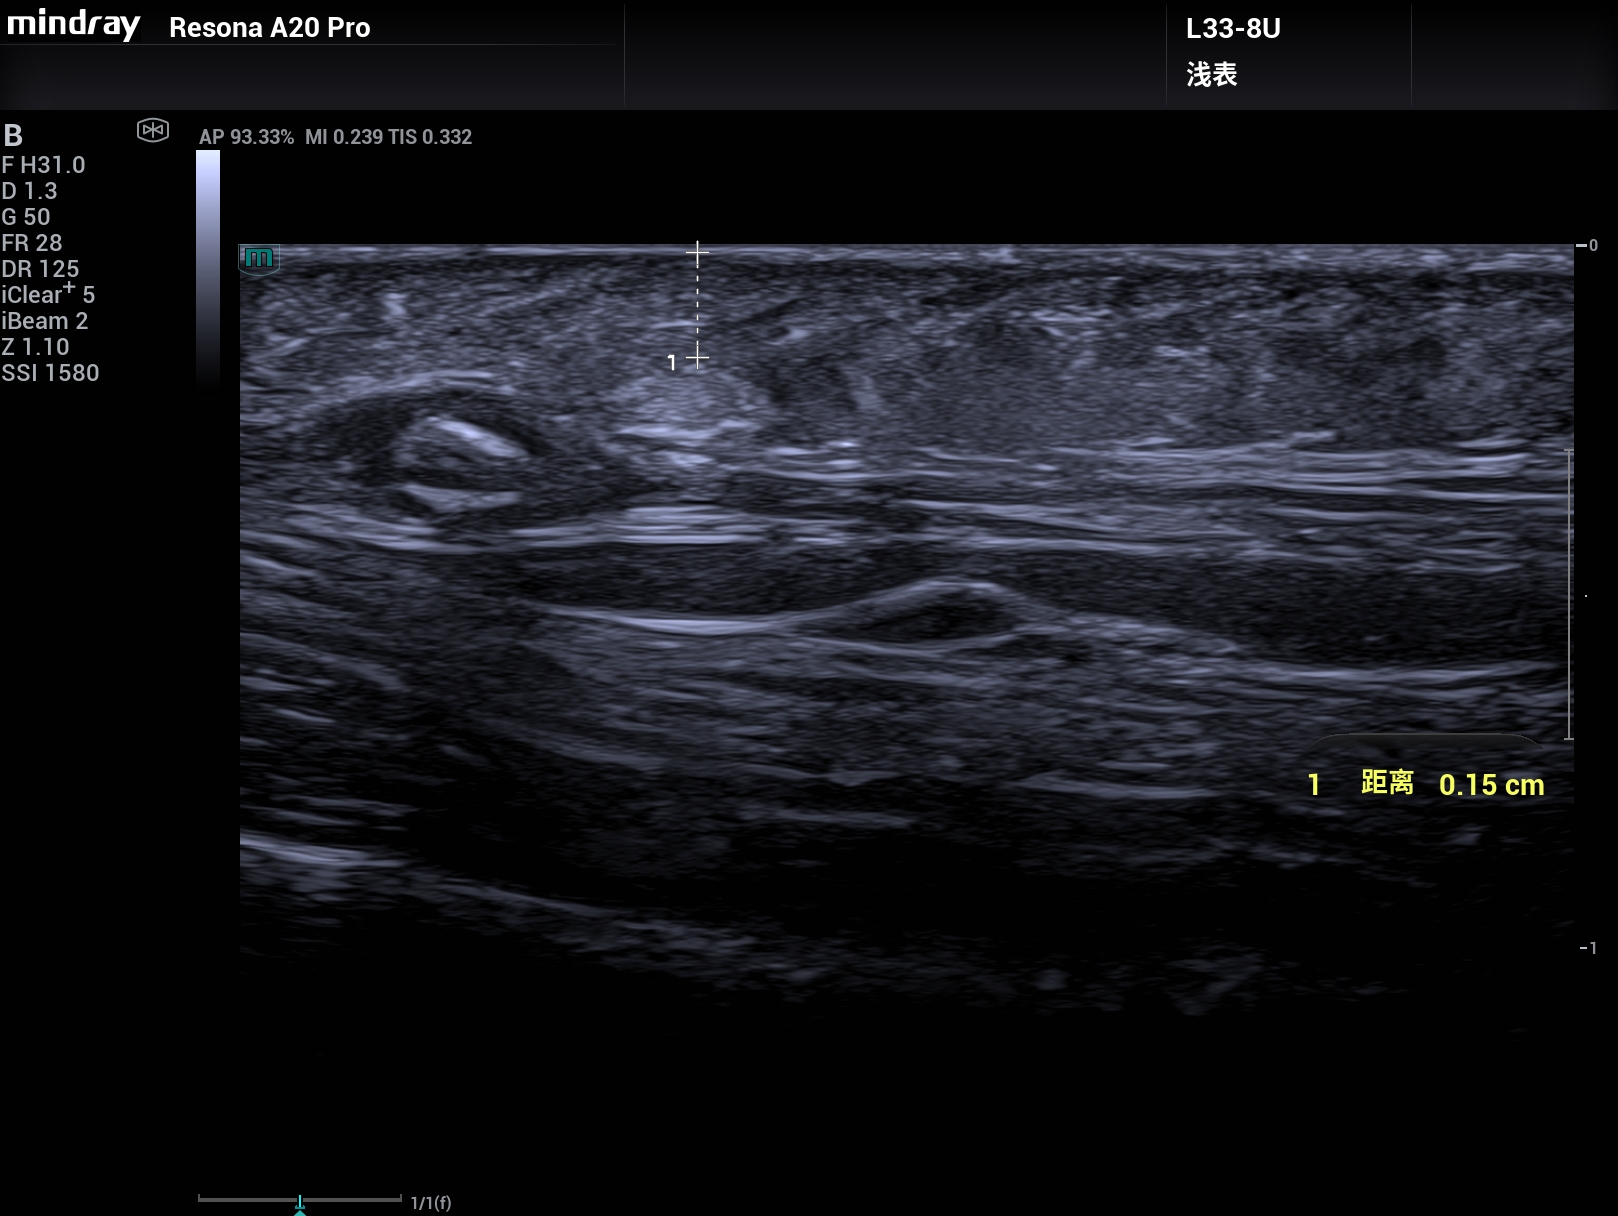

病例,33M和超微血流,头皮下1.5mm的2.6mm×1.1mm的脂肪瘤清楚显示,迈瑞Resona A20,2025年11月